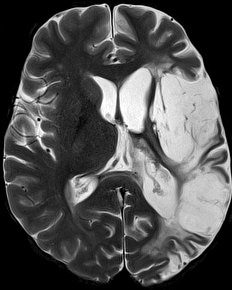

Neurolinguistics – Aphasia: Aphasia is an acquired language disorder characterized by difficulties in producing and understanding speech, in word finding, in reading and in writing. It may be accompanied by difficulties in arithmetic operations, in movements and in short-term memory. Aphasia is the result of brain damage that can arise from various causes (e.g. stroke). In our studies we examine problems in naming nouns and verbs as well as in producing and understanding speech, using timed (on line) tests (e.g. eye movement studies) and non-timed (off line) tests (e.g. speech extraction, truth value judgment, image selection). Our goal is to understand the deficits in language processing in individuals with aphasia.